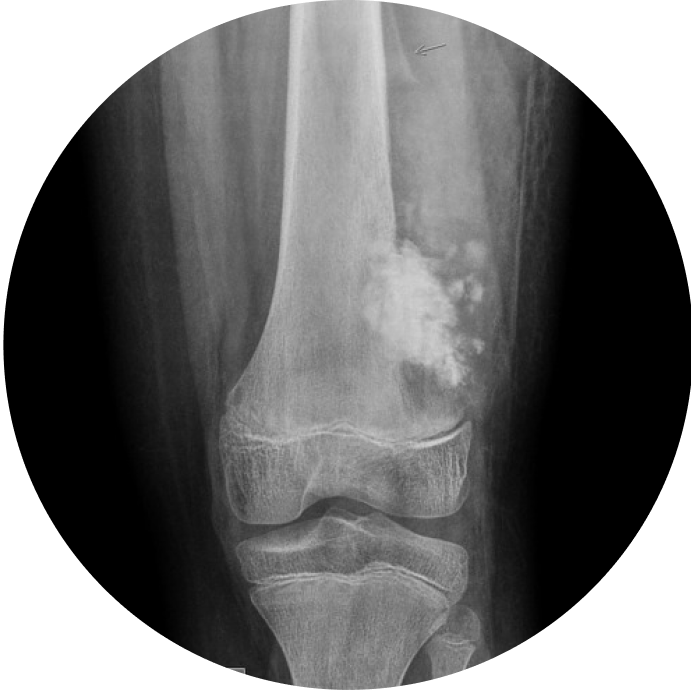

It evaluates various clinical parameters, including reduction in joint space, presence of osteophytes, sclerosis, tibial spikes, bone alignment, and post-operative conditions.

OsteoCheck is a diagnostic system that evaluates bone degeneration, categorizing severity into grades ranging from 1 to 4.